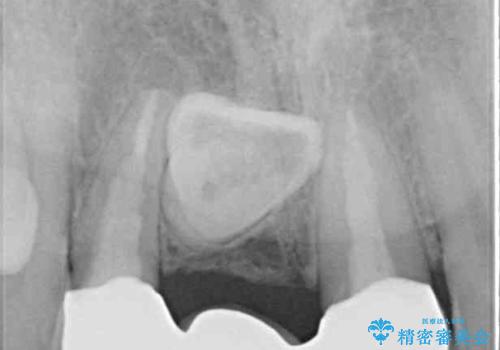

前院では、土台の金属を除去することは不可能であると言われたとのことでした。金属の土台が残っているとセラミックにグレーの金属色が透けて見えてしまうため、拡大鏡やマイクロスコープを用いて丁寧に除去し、天然歯の色に近いファイバーコアを植立することとしました。

また、歯とクラウンの境目が合っていない部分が多く、歯肉からの出血が認められました。